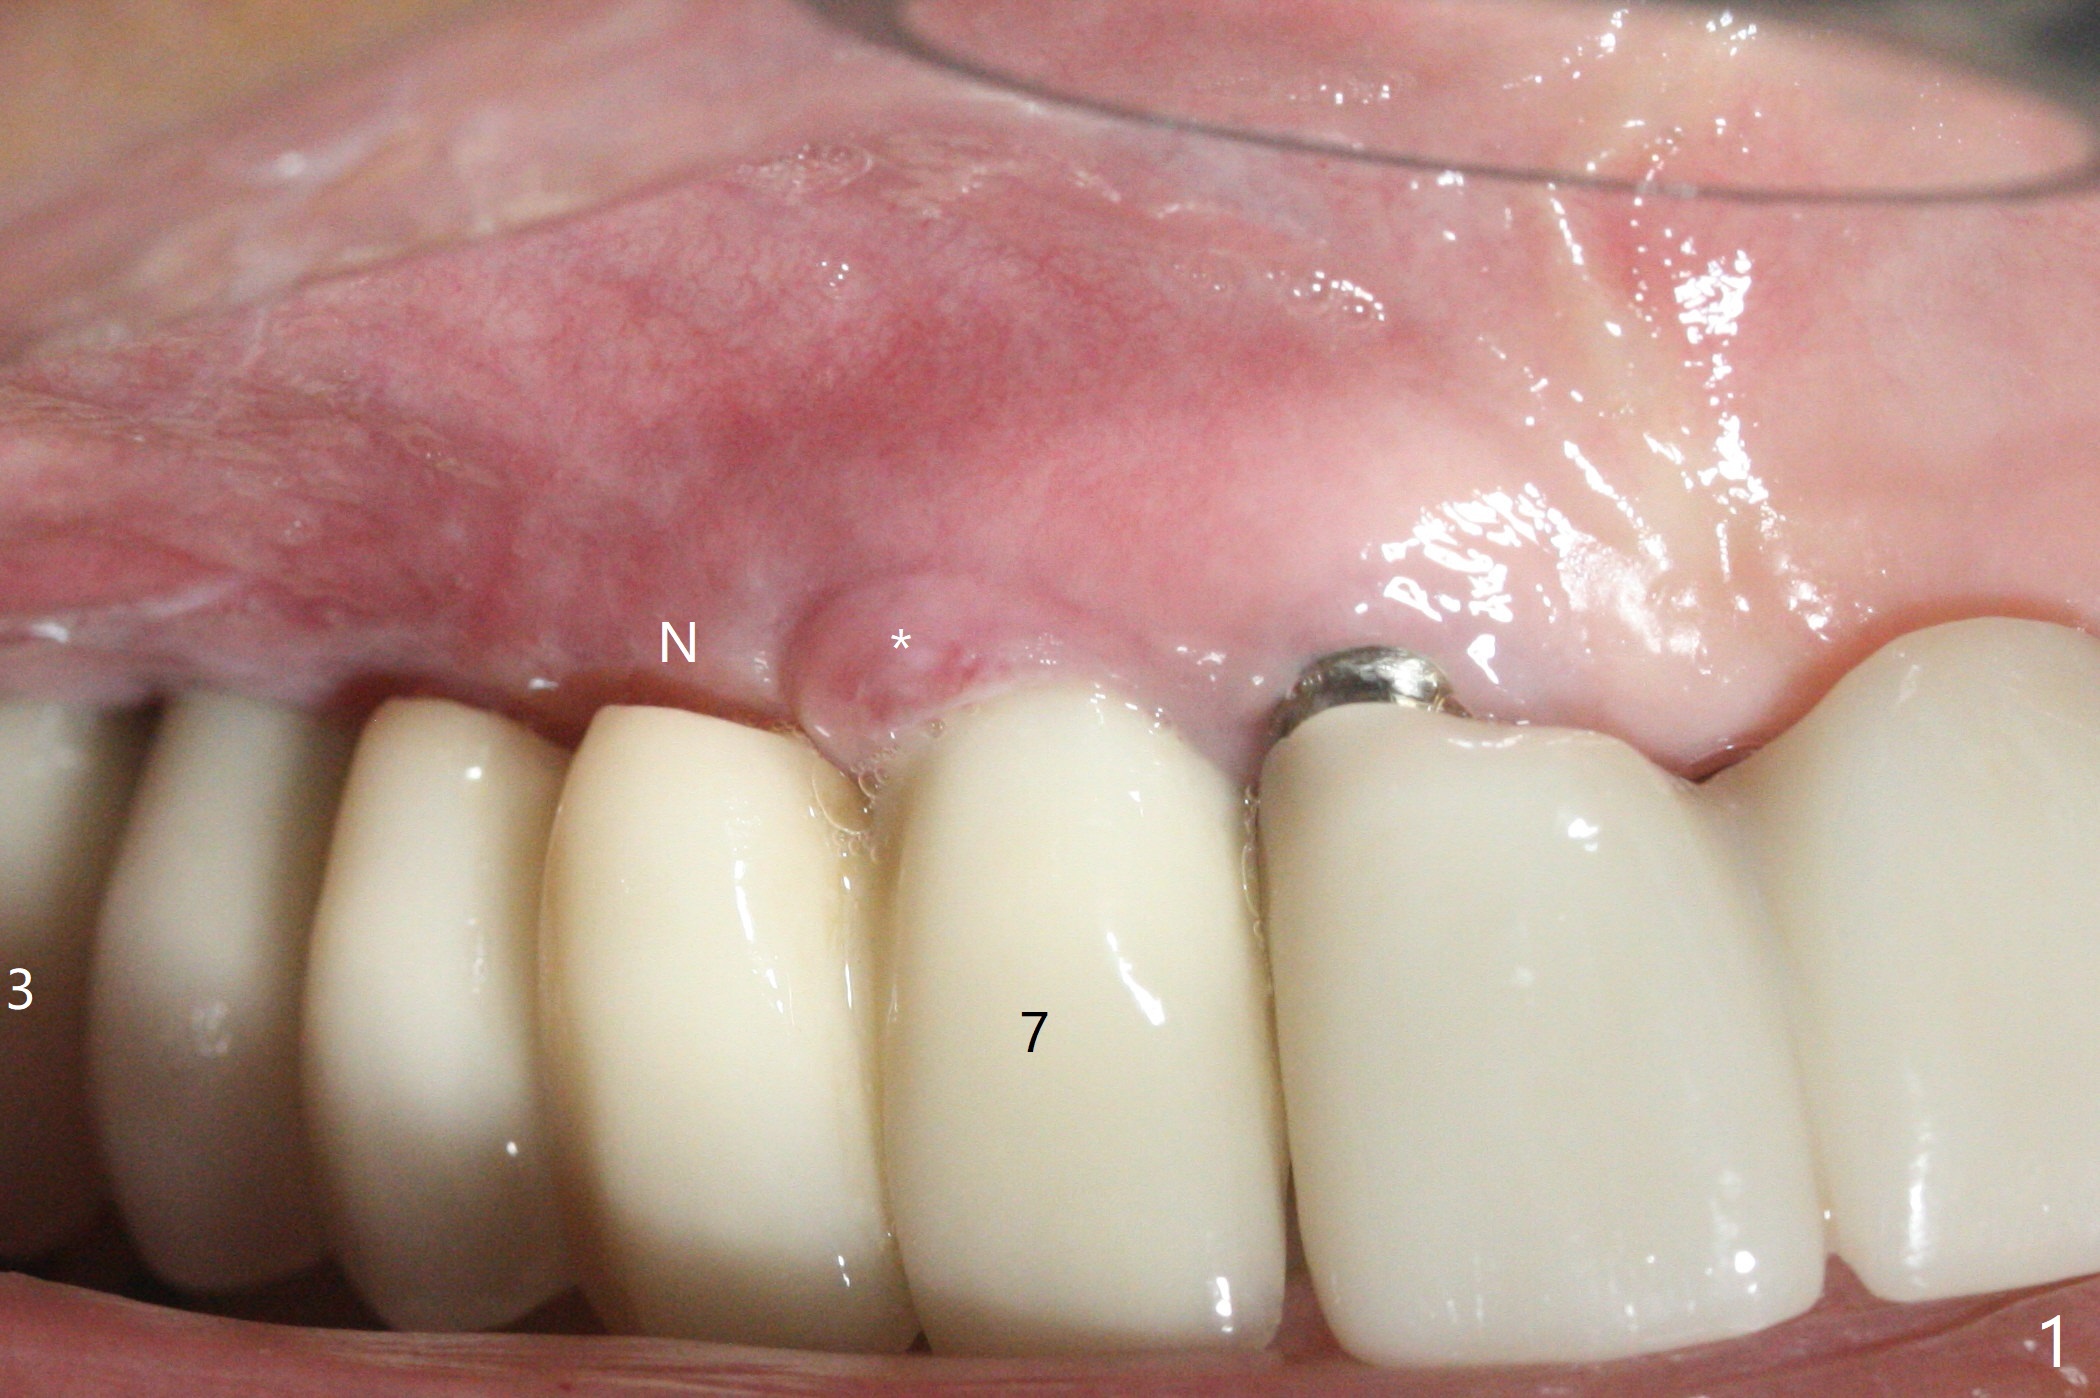

64岁女3-7牙桥,7号牙植体颊侧牙龈缘红肿(图一:*),脓液(图二:^),需要切开清洗,但是6号牙桥墩颊侧非角化龈(N)妨碍切口,所以必须去除桥墩,暴露牙槽嵴顶角化龈(图三:K),容易切开,最后缝合而不容易出血,伤口容易愈合。切开清创后重大发现是牙冠边缘(图四:^)直接接触植体微螺纹,没有基台与牙龈之间形成的屏障,有利于口腔细菌直接感染植体。直感告诉术者必须缩短牙冠边缘,抛光。然后缺损处放置粘性骨粉(图五,八:S,与图七(术前)比较),表面覆盖PRF膜,缝合(图六)。准备术后尽早去除牙冠,预防细菌再次感染。并且在6号牙位植入2x8.5毫米植体。